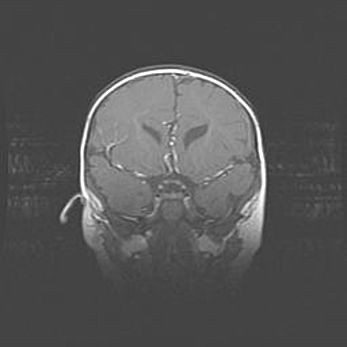

Открытая гидроцефалия.

Возраст: 6 месяцев 15 дней

Вес: 6200 г

Пол: женский

Окружность головы: 41 см

Срок гестации: 38 недель

Гидроцефалия головного мозга у новорожденных – это скопление избыточного количества цереброспинальной жидкости в головном мозге. Ее избыточное скопление в мозге приводит к патологическому расширению желудочков мозга (четырех полостей, расположенных в глубине белого вещества мозга, заполненных цереброспинальной жидкостью и связанных узкими проходами).

Открытый тип гидроцефалии (сообщающаяся) наблюдается тогда, когда нарушен механизм всасывания ликвора в системный кровоток. При этом типе причиной заболевания чаще всего является перенесенные ранее инфекции (например: менингит),  либо же наличие крови в субарахноидальном пространстве.